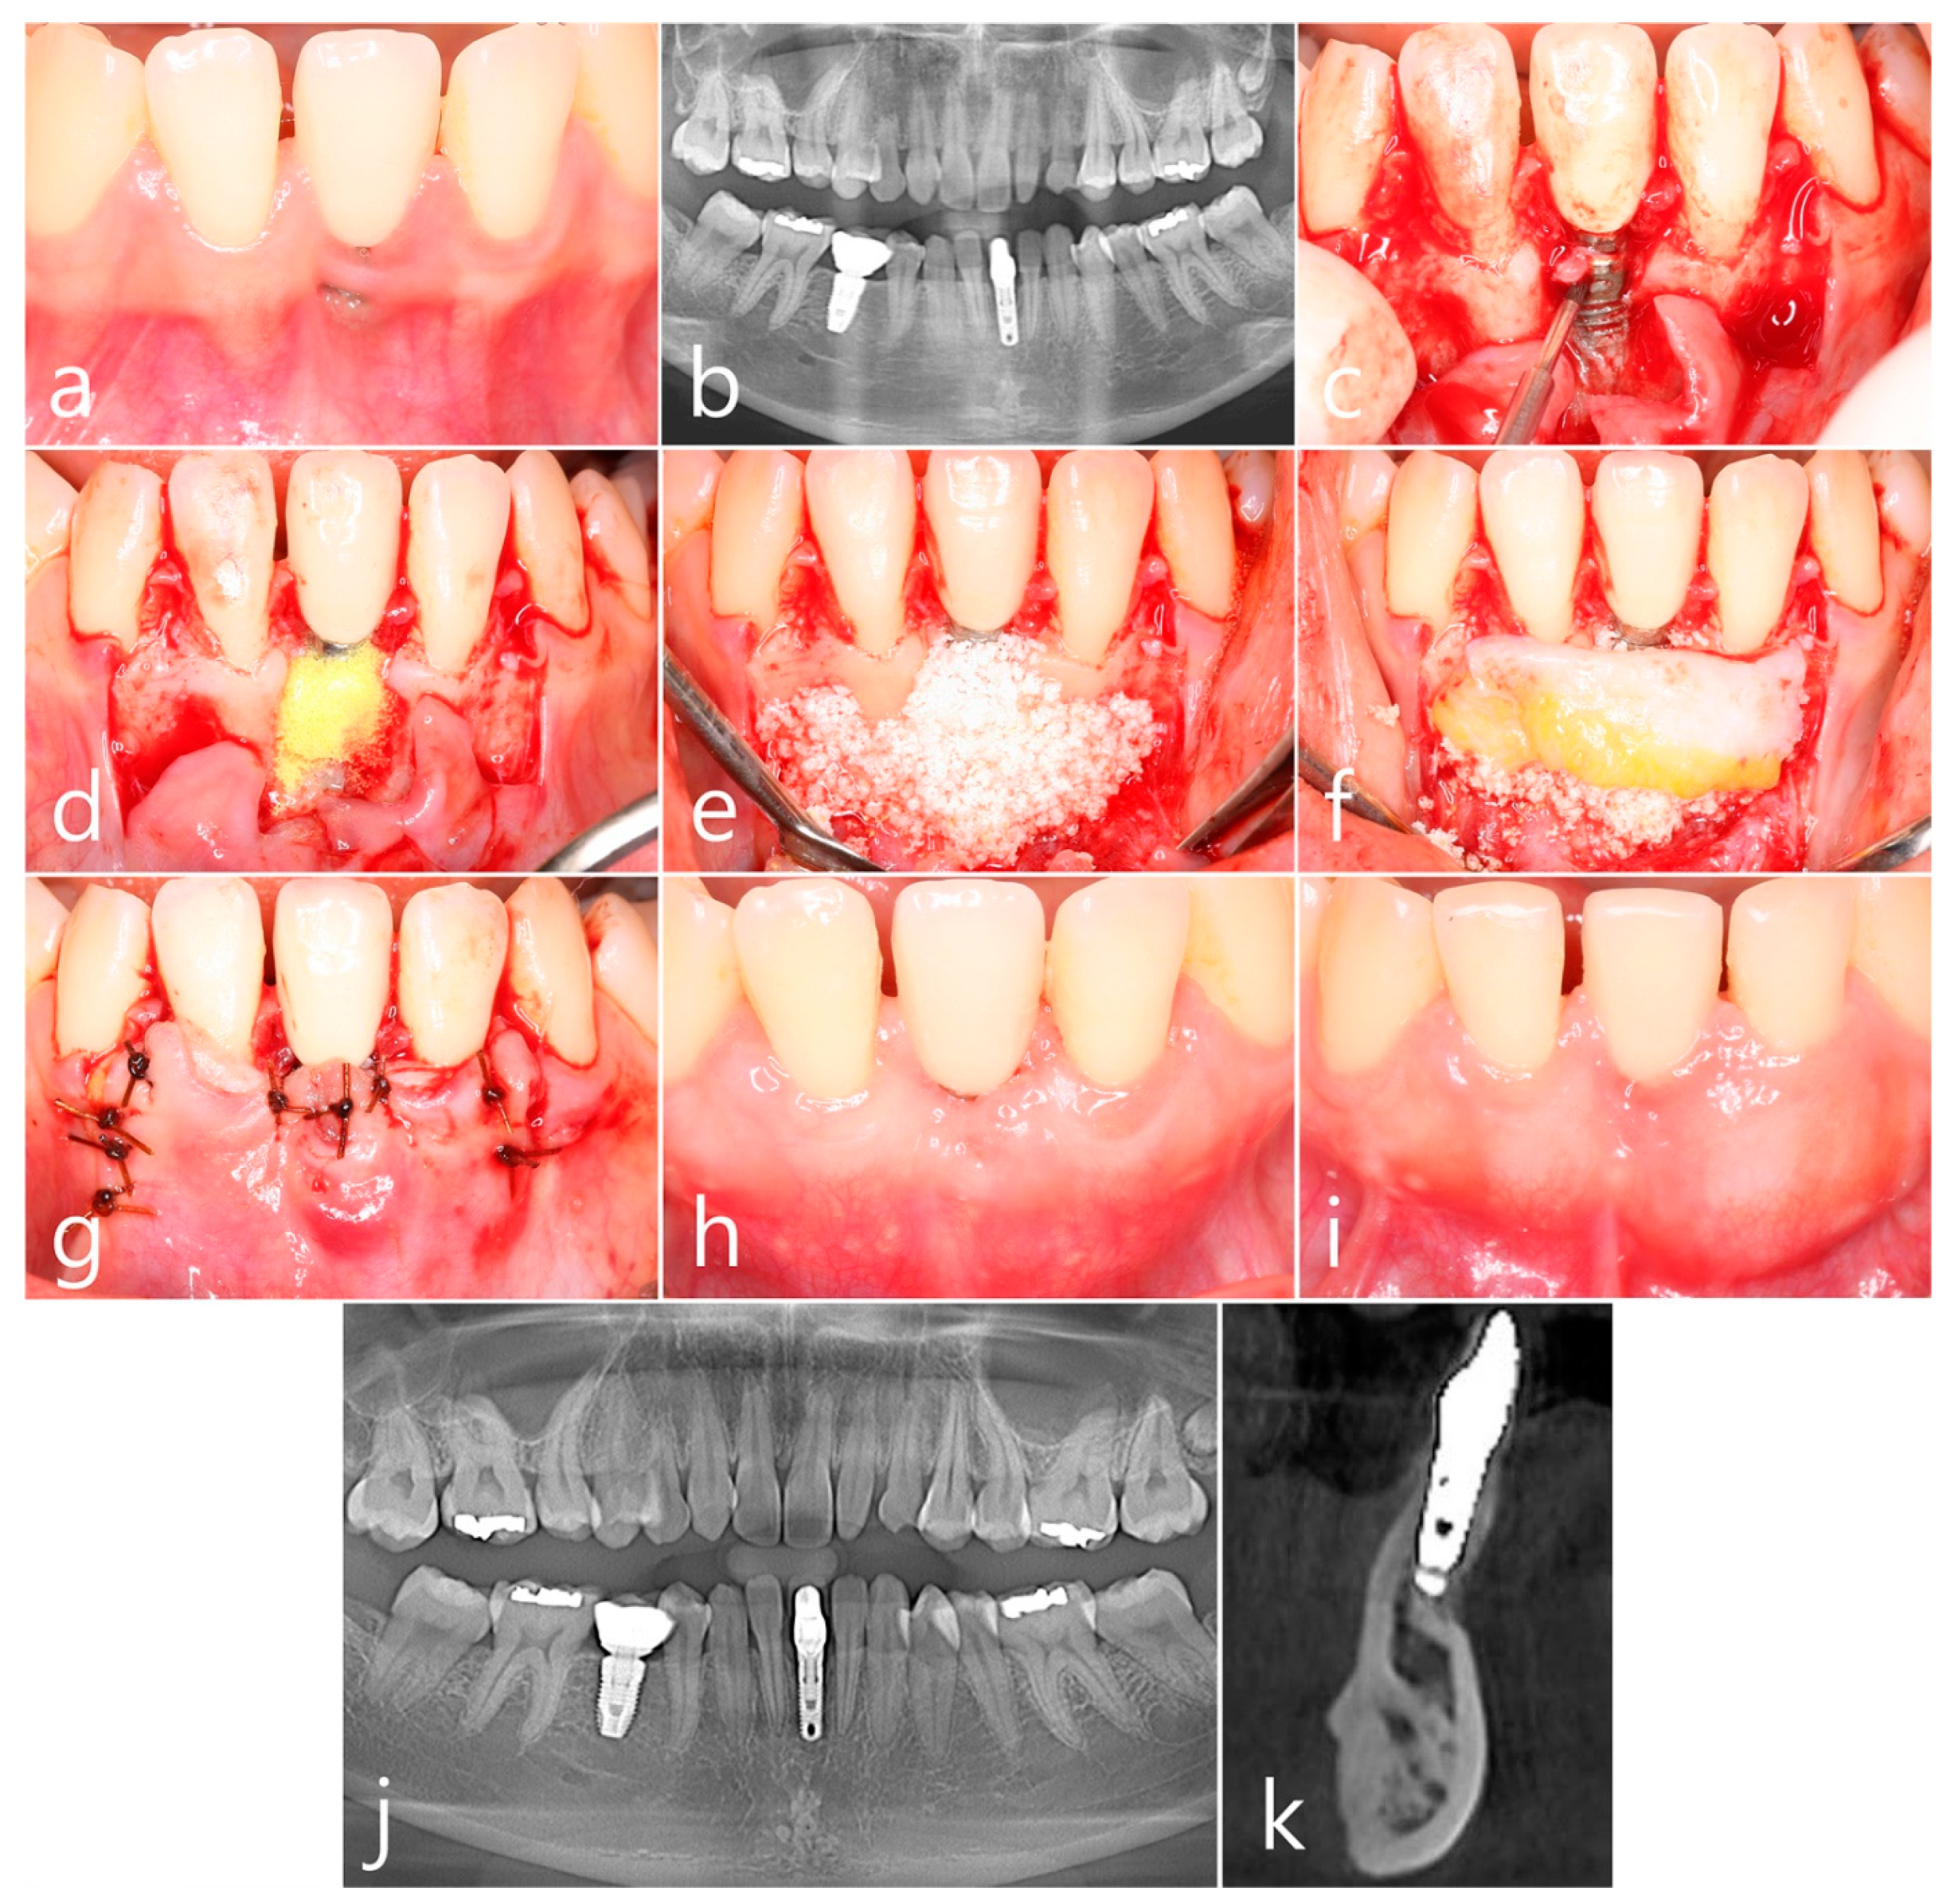

2.2. Case 2